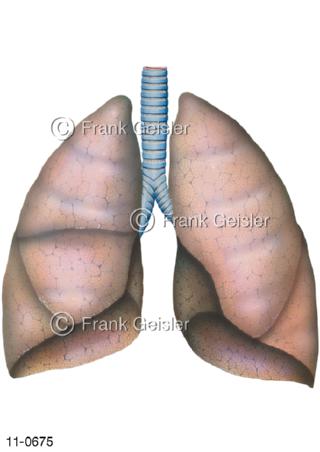

11-0675 Atemtrakt Luftröhre Trachea und Lungen